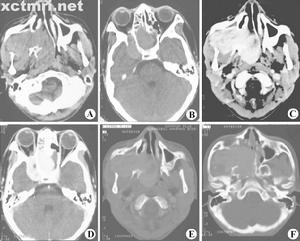

本DVD為“十五”國家重點音像出版規劃品種、衛生部醫學視聽教材。鼻咽纖維血管瘤為鼻咽部最常見的良性腫瘤,常發生於10-25歲青年男性,又稱為“男性青春期出血性鼻咽血管纖維瘤”。本DVD介紹了鼻咽纖維血管瘤的病理、臨床表現、診斷,主要介紹了手術治療過程:面中掀翻徑路、經硬齶徑路鼻咽纖維血管瘤手術,示範了減少術中出血的措施——頸外動脈結紮術,介紹了手術併發症和術後處理等內容。本DVD由山東大學齊魯醫院製作,片長38分鐘,適合於醫學院校師生及耳鼻咽喉科醫師使用。

鼻咽纖維血管瘤本病病因不明,多發於10歲~25歲的男性,女性少見。本病在病理上雖屬良性,但由於其生長擴展力強,常直接侵人周圍組織及器官(如鼻腔、鼻竇、翼齶窩、顳下窩、眼眶),甚至壓迫破壞顱底骨質侵入顱內,引起一系列症狀。反覆大量出血又可致嚴重貧血,常危及病人生命,故臨床表現實屬險症。

檢查可見到鼻腔後部及鼻咽部有表面光滑、呈粉紅色或紅色、表面有擴張血管的腫瘤。鼻咽部觸診,視瘤體所含纖維或血管的成分不同,質感亦有異:當纖維成分較多時則質感較堅韌;血管成分較多時,則較柔軟。基底廣泛、固定。指診時動作要輕柔,以免引起出血,在進行檢查前要作好止血準備。